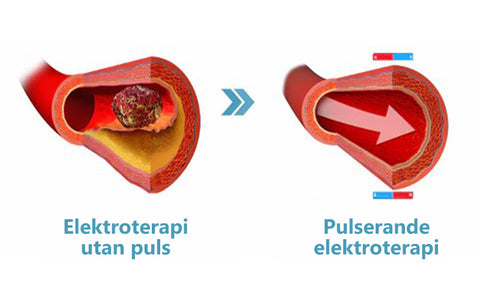

Lågfrekvent pulsad elektroterapi (LF-PEMF-terapi)

LF-PEMF-terapi är en teknik som använder lågfrekventa pulsade elektriska strömmar för att stimulera nerver och muskler. Det kan användas för att lindra smärta, förbättra blodcirkulationen, minska muskelspasmer och hjälpa till att återställa muskel- och nervfunktioner. LF-PEMF-terapi används i stor utsträckning inom sjukgymnastik och rehabilitering i USA och är erkänt som en effektiv icke-invasiv behandling.